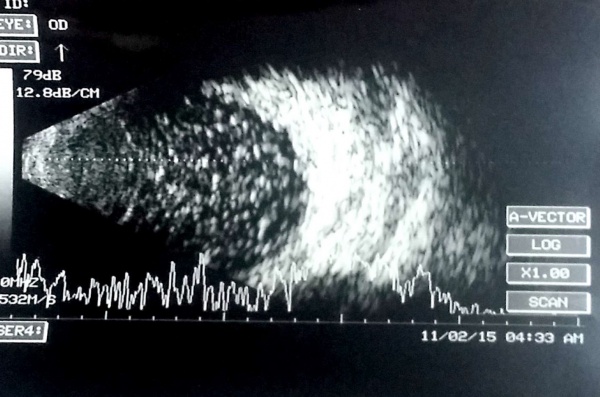

[The funnel RD is attached to the disc and is not showing after-movements with ocular movements.]